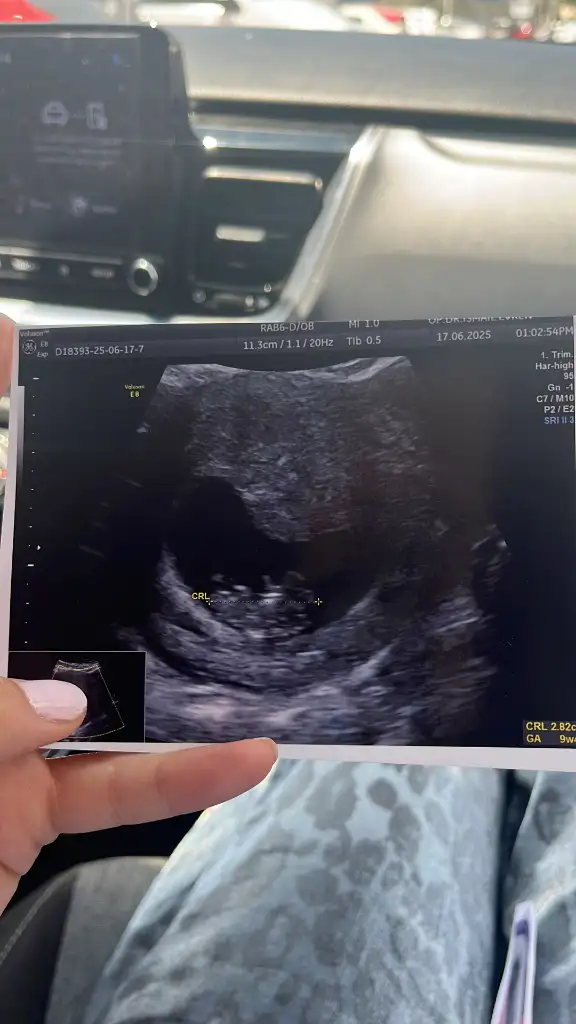

Bana da bakar mısınız lütfen biri 9 haftalık biri 6 haftalık karından ultrasonKese şekline göre erkek bence. Sağlıkla kucağınıza alın

Banada bakar mısnız lütfennnn çok merak ediyorum biri 9 haftalık biri 6 haftalık ultrason karından

Erkek bence. Sağlıkla kucağınıza alınBana da bakar mısınız lütfen biri 9 haftalık biri 6 haftalık karından ultraso

link atar mısınYapay zekayada sordum 6 haftalık ve 8 haftalik iki resmede erkek dedi Rabbim nasip etsin inşallah

Tahmin edebilirmisiniz rica etsemErkek bence. Sağlıkla kucağınıza alın

Sanırım erkek sizinkiTahmin edebilirmisiniz rica etsem